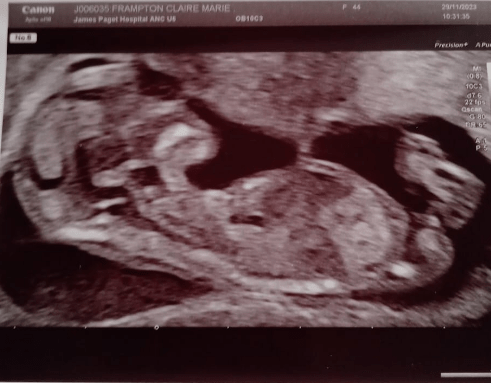

We met Andy and Claire. It’s the first time we had seen them since Claire’s recent social media announcement that she’s expecting a new addition to the family in June 2024. Expecting… but unexpected. This will be their tenth child.

A shock to the system, who will be loved and welcomed to their family.